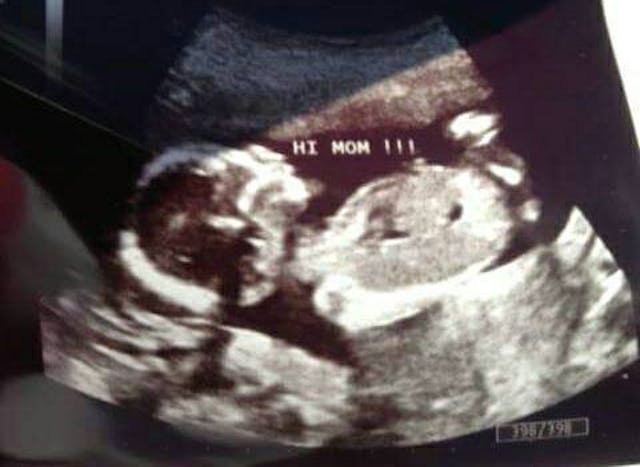

Pam explained to the woman that the ultrasound picture only showed her child’s head, and the would-be abortion patient was surprised. She agreed to accompany Pam to have a free ultrasound. The free ultrasound showed the whole baby. This is a photo from that ultrasound:

After seeing what her baby really looked like, the woman chose life.